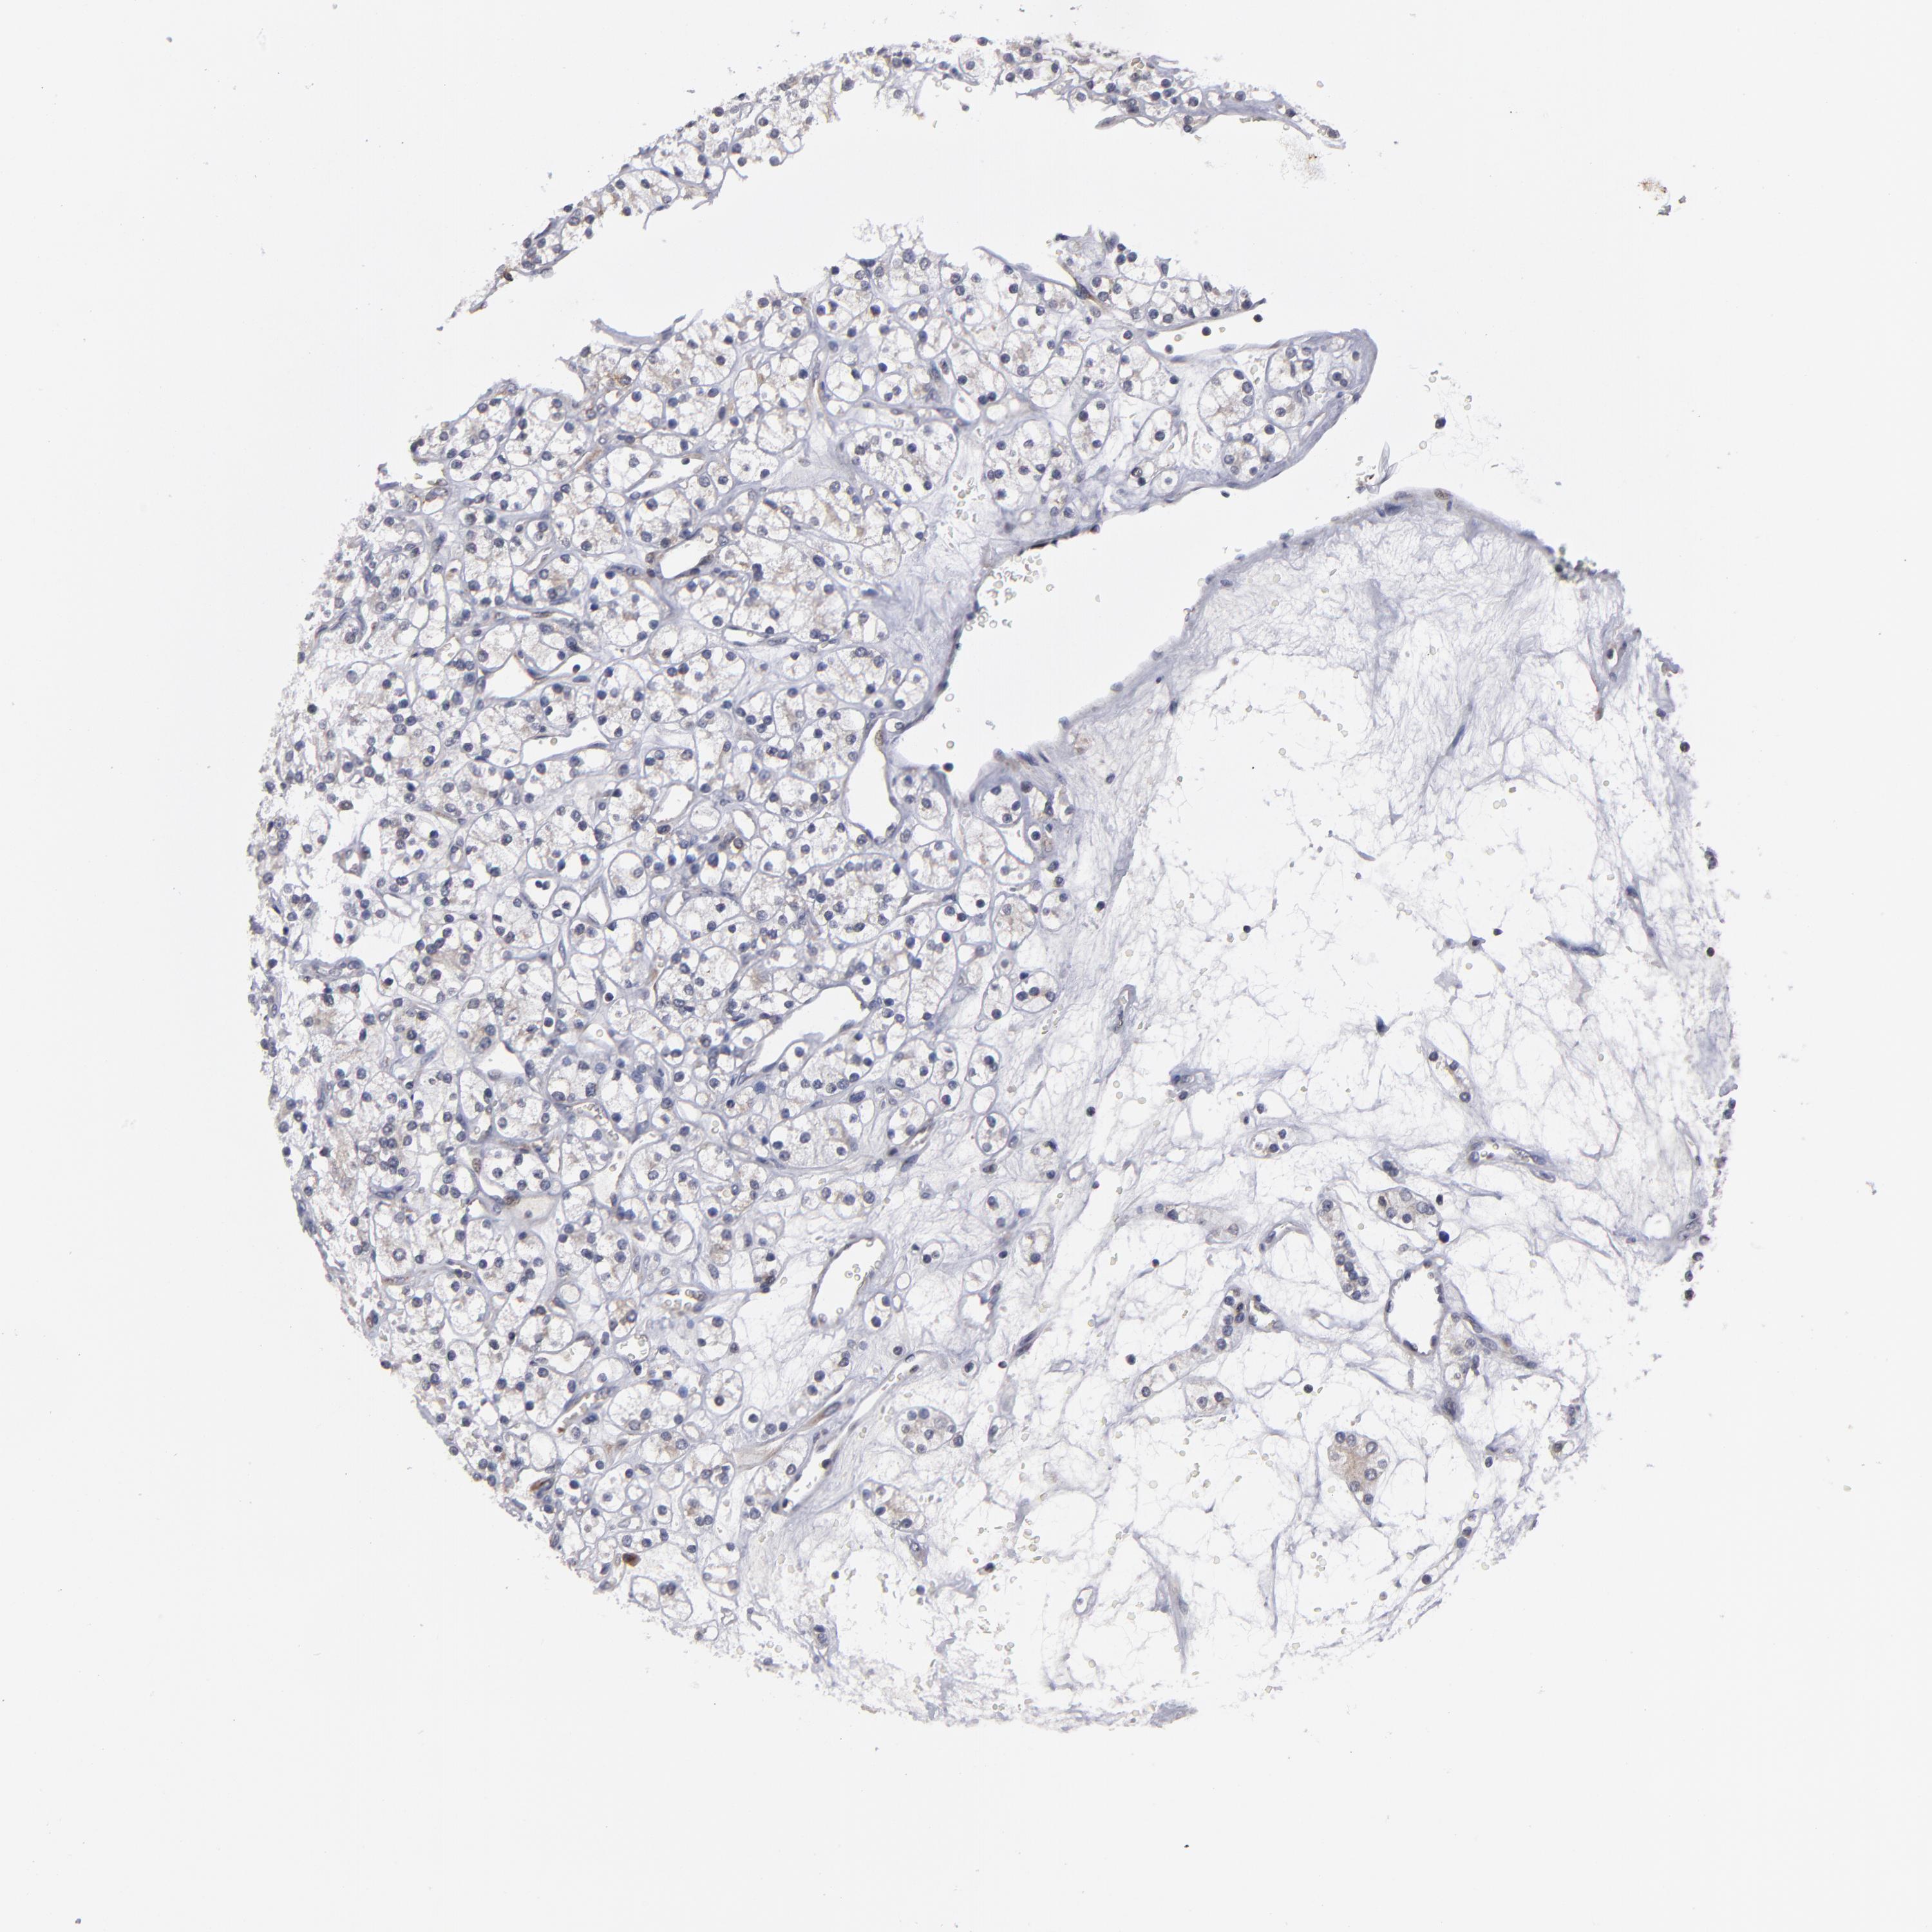

KIDNEY RENAL CLEAR CELL CARCINOMA (VALIDATION) - Interactive survival scatter ploti

The Survival Scatter plot shows the clinical status (i.e. dead or alive) for all individuals in the patient cohort, based on the same data that underlies the corresponding Kaplan-Meier plots. Patients that are alive at last time for follow-up are shown in blue and patients who have died during the study are shown in red.

The x-axis shows the expression levels (FPKM) of the investigated gene in the tumor tissue at the time of diagnosis. The y-axis shows the follow-up time after diagnosis (years). Both axes are complimented with kernel density curves demonstrating the data density over the axes. The top density plot shows the expression levels (FPKM) distribution among dead (red) and alive patients (blue). The right density plot shows the data density of the survived years of dead patients with high and low expression levels respectively, stratified using the cutoff indicated by the vertical dashed line through the Survival Scatter plot. This cutoff is automatically defined based on the FPKM cutoff that minimizes the p-score. The cutoff can be changed by dragging the vertical line or by entering a cutoff value in the square labeled "Current cut-off".

Under the Survival Scatter plot the p-score landscape (black curve; left axis) is shown together with dead median separation (red curve; right axis). Dead median separation is the difference in median mRNA expression between patients who have died with high and low expression, respectively. It is calculated as follows: median FPKM expression of dead patients with high expression - median FPKM expression of dead patients with low expression. This is intended to aid the user in visually exploring custom cutoffs and the associated p-scores and dead median separation.

Individual patient data is displayed and can be filtered by clicking on one or more of the category buttons on the top of the page. Categories describing expression level and patient information include: high, low, alive, dead, female, male and tumor stages. The scale of the x-axis can be toggled between linear and log-scale by clicking on the "x log" button. Mouse-over function shows TCGA ID, patient information and mRNA expression (FPKM) for each patient.

& Survival analysisi

Kaplan-Meier plots summarize results from analysis of correlation between mRNA expression level and patient survival. Patients were divided based on level of expression into one of the two groups "low" (under cut off) or "high" (over cut off). X-axis shows time for survival (years) and y-axis shows the probability of survival, where 1.0 corresponds to 100 percent.

CEP97 is not prognostic in Kidney Renal Clear Cell Carcinoma (validation)

: 3.01

Average pTPM 3.1

Number of samples 100